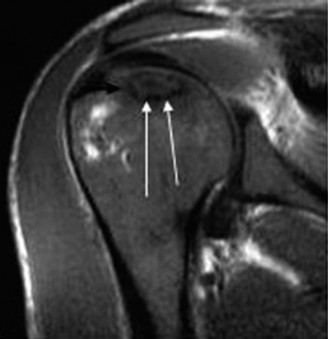

Thorough pre-operative planning begins with advanced imaging. While the initial ED evaluation mandates true orthogonal radiographs (AP and Axillary views) to confirm joint concentricity and rule out fractures, definitive surgical planning requires cross-sectional imaging. Magnetic Resonance Imaging (MRI), preferably an MR Arthrogram with intra-articular gadolinium, is the gold standard for evaluating the soft tissues. It allows for the precise identification of Bankart, ALPSA, and SLAP lesions, assesses the volume and integrity of the capsular tissue, and evaluates the rotator cuff.

To accurately quantify bipolar bone loss, a non-contrast 3D Computed Tomography (CT) scan with digital subtraction of the humeral head is mandatory. Glenoid bone loss is calculated using the "best-fit circle" method on the en face sagittal view of the glenoid. The width of the inferior glenoid is compared to the expected diameter of the intact posterior rim. Simultaneously, the Hill-Sachs lesion is evaluated to determine if it is "on-track" or "off-track." The glenoid track is calculated as 83% of the intact glenoid width, minus the measured anterior glenoid bone loss. If the medial margin of the Hill-Sachs lesion extends medial to this track, it is deemed "off-track" and will engage the anterior glenoid rim during abduction and external rotation, necessitating either a Remplissage or a Latarjet.

Clinical & Radiographic Imaging Archive